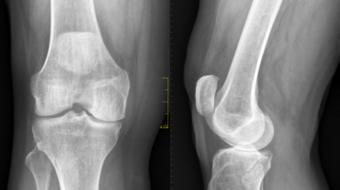

Orthopaedic Surgeon, discusses PRP (Platelet Rich Plasma) to Treat Orthopedic Conditions including Osteoarthritis

Featuring Dr. Jas Chahal, MD, MSc., FRCSC, Orthopaedic Surgeon PRP (Platelet Rich Plasma) to Treat Orthopedic Conditions including Osteoarthritis